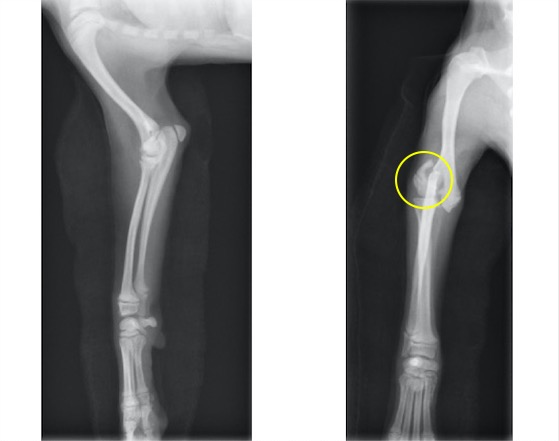

単純X線画像上の成長板(前肢と後肢) 矢印が成長板です。

柴犬 雌 6ヵ月齢

自転車の後部座席より落下、右前肢の挙上を主訴に来院。

触診上、手根部の腫脹と圧痛が認められました。

単純X線画像検査上、ラテラル像では大きな左右差は認められませんでしたが、AP像にて軟部組織の腫脹と成長板の間隙が広くなっていることから橈骨遠位成長板骨折(Salter-Haris Type1)と診断し、外科的処置を行いました。

初心時のX線画像検査初見 赤矢印:軟部組織の主張、黄矢印:橈骨遠位成長板(左前肢と比較すると成長板の間隙が広い)